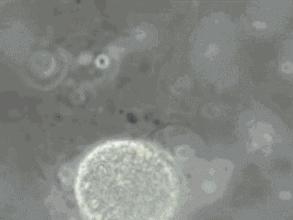

在卵子的外面

有一层极其致密的结构

这透明带

就是这个BUG

精子可以利用自己的“头顶”

(专业术语叫顶体)

在透明带上溶出一个洞让精子穿过

但是!!!

一个精子是不足以溶穿透明带的

要很多精子齐心协力才行

而且!!!

只要有一个精子穿过了透明带

透明带就会迅速锁闭

不再让第二个精子进入